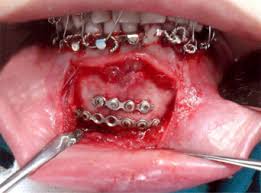

• Oral & maxillofacial surgery Department

Oral & Maxillofacial Surgery :

• Oral cancer Treatment

• Operation of oral cyst &tumour

• Jaw fracture management

• Treatment for oral ulcer, infections

• Temporomandibular joint disorder treatment